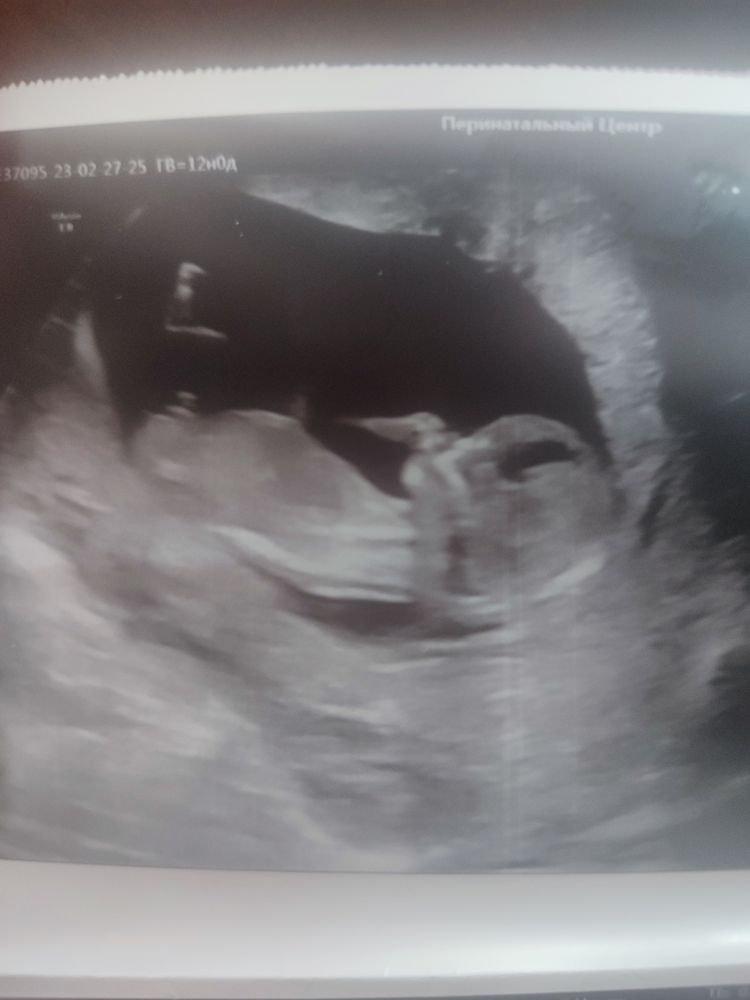

Пол ребёнка 1скрининг 12нед

Девочки, ну подскажите кто профи по снимкам это Парнишка? 🙈по узи 12.4 а по местам ровно 12 нед. Ну конечно я поставила уже значок паршишки🙈

Пацан! У моей дочки половой бугорок был параллельно позвоночнику. А у вас явно видно что угол другой))